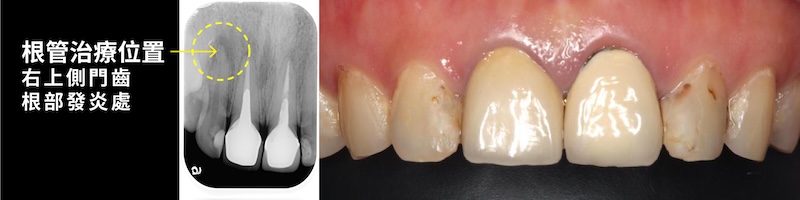

2016 年進行根管治療後,以全瓷冠修復蛀牙受損門牙。